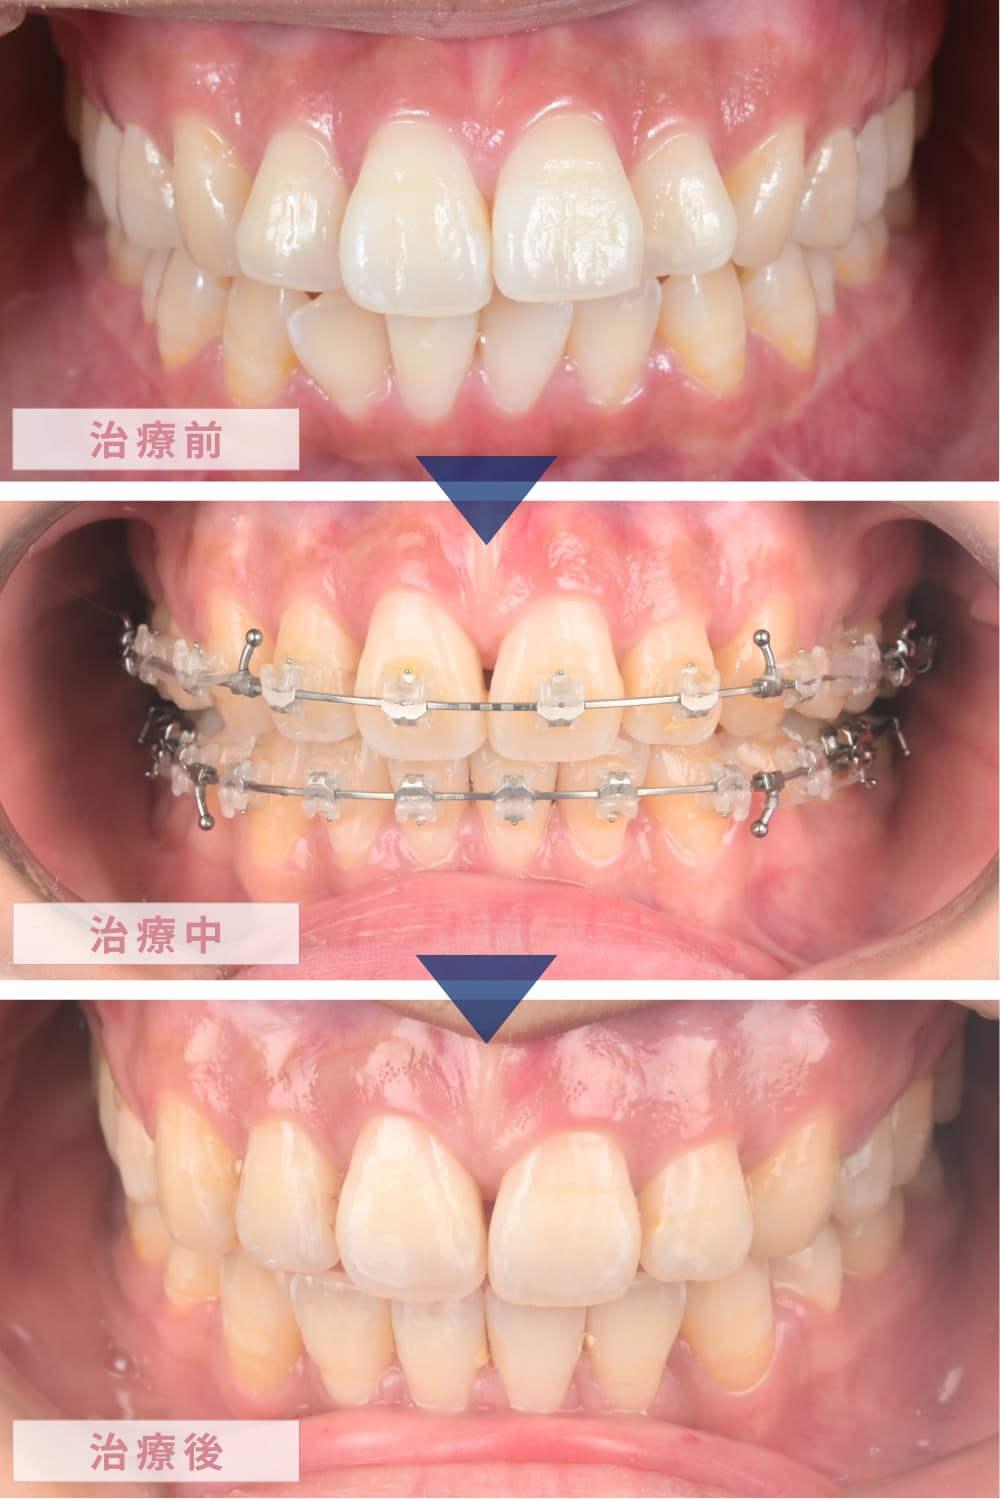

【治療経過画像】

《正面》

約30回の通院を経て、動的治療(歯を動かす期間)が終了しました。

治療後は、ご本人の一番の悩みであった「口元の突出感」がなくなり、力を入れなくても自然に口が閉じられるようになりました。横顔のEラインも非常に美しく整い、コンプレックスが解消されたことで、患者さんの表情がとても明るくなられたのが印象的でした。

検査の結果、ご本人が気にされていた通り、前歯部の突出感があり、唇を閉じる際にオトガイ(顎の梅干しジワ)に緊張が見られました。